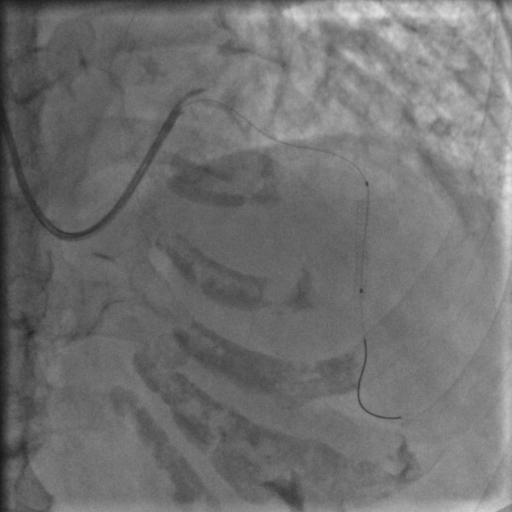

还是没通,这个也很正常。那就再拿球囊走一下,送入2.5*15mm的PTCA球囊,走得很顺,可以沿着导丝走到前降支远端,反复地走几次,看看能不能把血栓冲散,造影:

图8

还是没通,那就要来个血栓抽吸导管了,把球囊退出来,送入血栓抽吸导管到闭塞段,开始抽吸,一管、两管、三管,好了,看起来抽出来注射器里面都是血栓,抽吸的过程中似乎出现了一过性的心率变慢,应该是再灌注心律失常,应该通了吧,造影:

图9

好像前降支的显影是比刚才多出来一小节,然而依然还没通,那拿个球囊扩一下吧,把刚才的球囊送到闭塞段,2、4、6个大气压,轻轻扩一下,再轻轻扩一下,好松开,再打点硝酸甘油,造影: